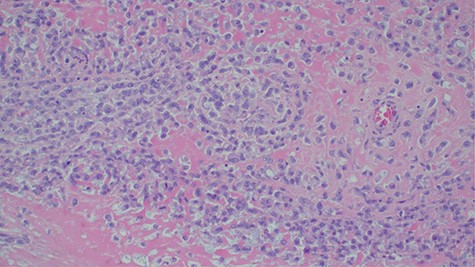

Laboratory investigations revealed a low platelet level of 53 per microliter and hemoglobin level of 10.7 g/dl. Renal profile, white blood count and serum electrolytes were within normal range. Computed tomography intravenous urogram revealed a large heterogeneous mass, measuring 5.5 × 4.5 cm at the right superolateral aspect of the urinary bladder with ipsilateral hydronephrosis and hydroureter. Bone scan study was unremarkable. Urothelial cell carcinoma of the urinary bladder was clinically suggested as the most likely differential diagnosis. Cystoscopy was done under spinal anesthesia, which revealed a solid mass with areas of necrosis at the anterior bladder wall. The biopsy was taken whose histological evaluation revealed a high-grade malignant mesenchymal tumor made up of oval or spindle cells with osteoid formation in many areas of the lesion (Fig. 1). No definite carcinomatous component was appreciated. The tumor was strongly positive for vimentin immunohistochemistry staining (Fig. 2) and negative for cytokeratin 20. Calcified schistosomal ova were also seen (Fig. 3).

Histopathology of urinary bladder tumor showing oval- to spindle-shaped cells with abundant osteoid matrix deposition (H&E stain, ×200).